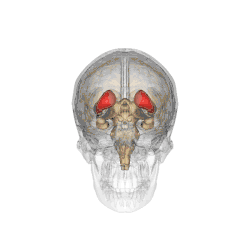

rose = noyau caudé et putamen, orange = thalamus